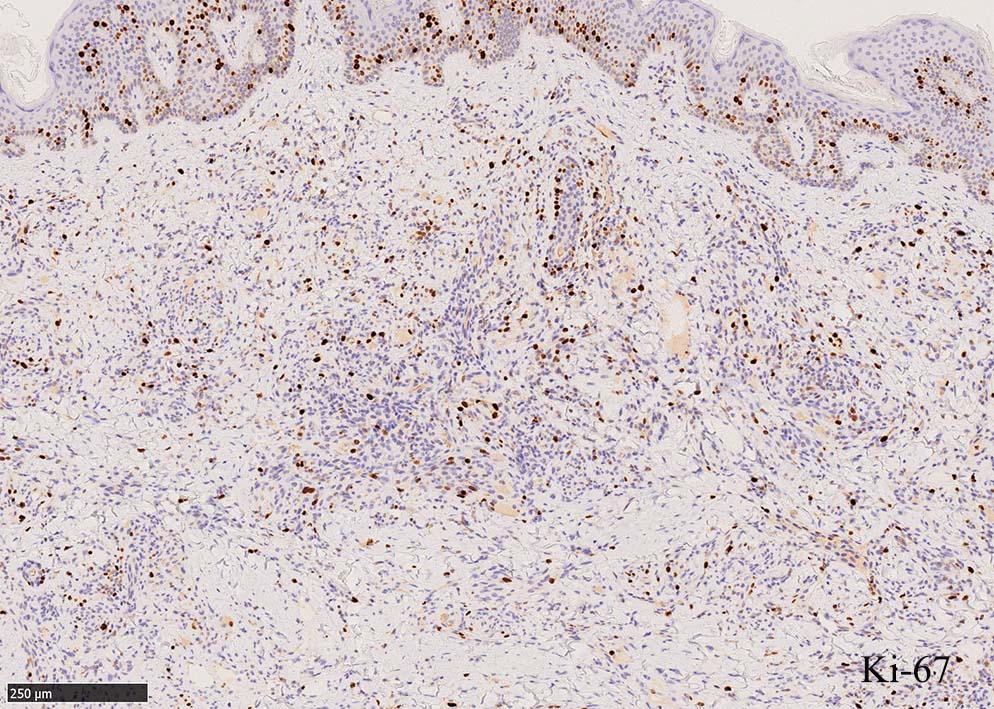

結節性病変の形成

紡錘形細胞が著しく増生し束状に走行する部分と, 内皮細胞様細胞による多数の小管腔構造が巣状にひろがり, 一見, 線維腫と血管腫が混在しているように見える. 一部の症例を除き, これらの増生細胞は異型性に乏しいことが多い.

免疫染色, 分子病理学的検査

増生細胞はCD31, CD34, Factor Ⅷ, D2-40などが陽性を示す.